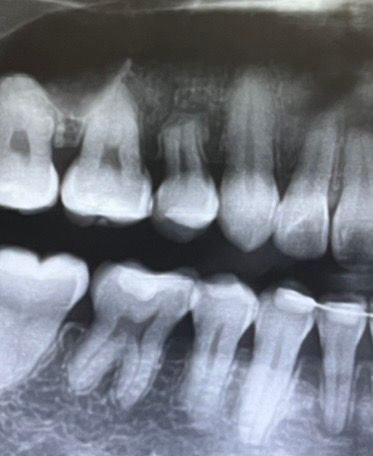

엑스레이를 보면 확실히 어금니와 아래 앞니는 많이 꺼진 것 같고, 송곳니쪽 부분은 덜 꺼져있는데.. 필요없는 곳을 잇몸치료하면 잇몸이 더 내려간다는 말을 어디선가 들어본적 있어 걱정이 됩니다.

잇몸치료는 치석을 제거해서 염증을 없애는 것 같은데, 만약 교정으로 인해서 잇몸뼈가 내려간거라면 꼭 잇몸치료가 필요한걸까요? 아니면 잇몸뼈가 내려간 원인 = 무조건 치석일까요?

현재 느끼기에 씹는 힘도 약해져 있는 상황인데, 한번 깨끗하게 잇몸치료 받는게 좋은 상황일까요? 괜히 잇몸 건드리면 더 내려갈까봐 걱정되어 질문해봅니다ㅠㅠ + 제일 좋지 않은 잇몸쪽 사진 같이 올려둡니다

• 2번 째 사진